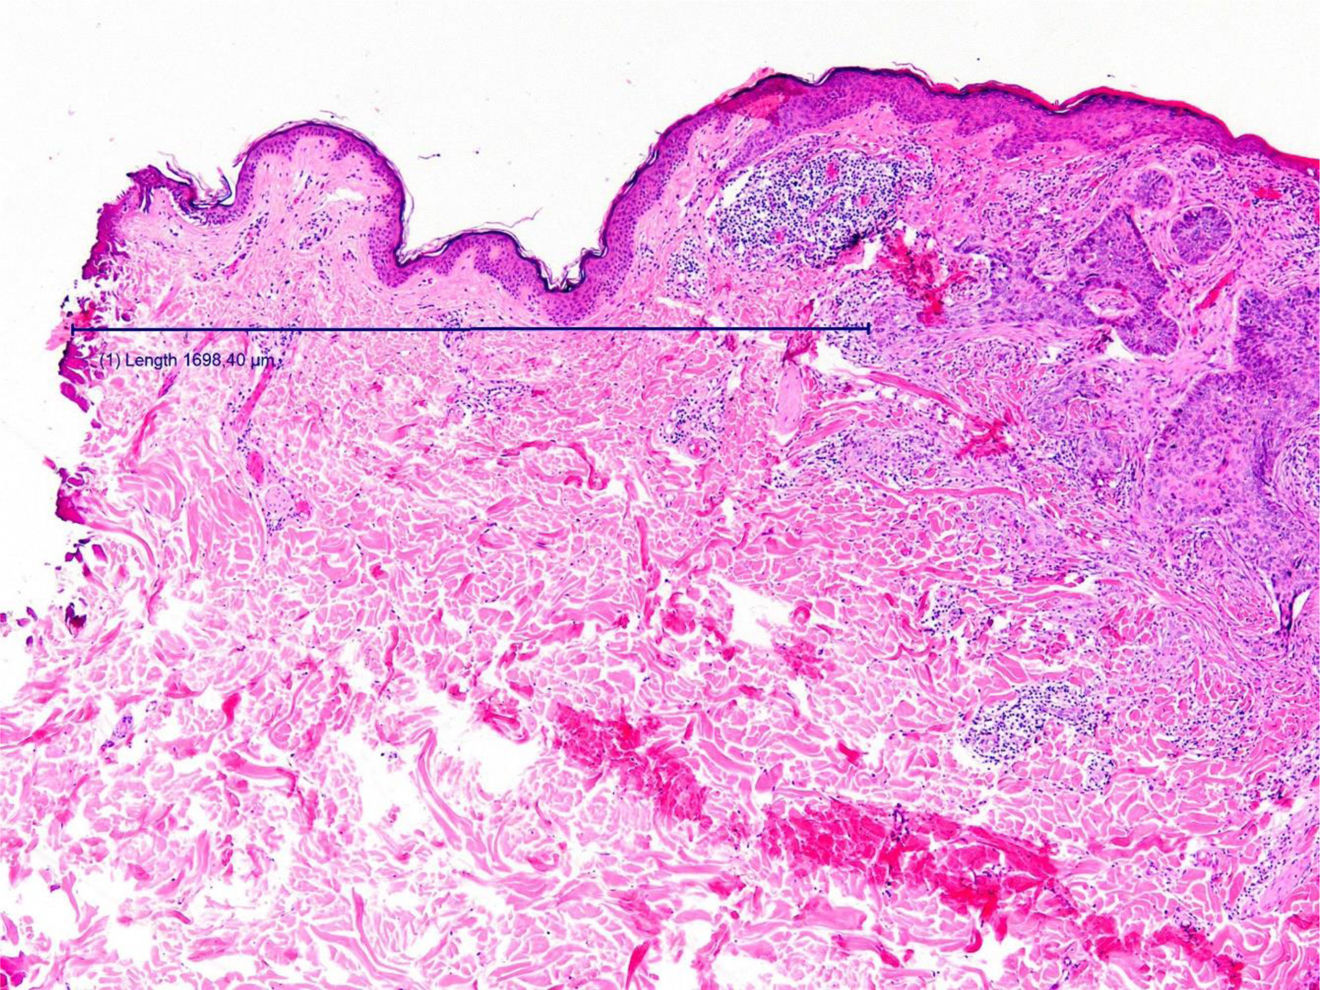

Former studies have compared these two cutting instruments according to different parameters such as speed, safety, and aesthetic outcome.4 However, studies comparing these instruments in the excision of skin tumors and their impact on resection margins were lacking. In our study, the resection margin was on average approximately 0.4mm closer to the carcinoma when the incision was performed with electrocautery. This difference is expected given the intrinsic mechanism of action of electrocautery. Histologically, tissue damage due to thermal dispersion is observed as coagulative necrosis in the form of an irregular eosinophilic band in the tissue (Fig. 2), whose thickness was not quantified as this was not the objective of the study.5 However, despite this artifact, no statistically significant differences were found in the resection margins between the two procedures. Therefore, although the use of electrocautery as a cutting instrument in the epidermal–dermal plane is often argued against because of the artifacts that thermal tissue damage may produce in the tissue, it has been observed that the application of recommended safety margins, rather than the cutting instrument per se, is what may guarantee a detailed histopathological analysis.

Image of the surgical specimen resected with an electrosurgical scalpel after H&E staining. The line represents the distance between the lateral edge of the tumor and the lateral resection edge, that is, the resection margin. Of the two resection margins resulting from transverse sectioning of the surgical specimen, only the closest margin was included in all cases. Note the coagulative necrosis in the form of an irregular eosinophilic band generated by the ultrafine-tip electrosurgical scalpel.